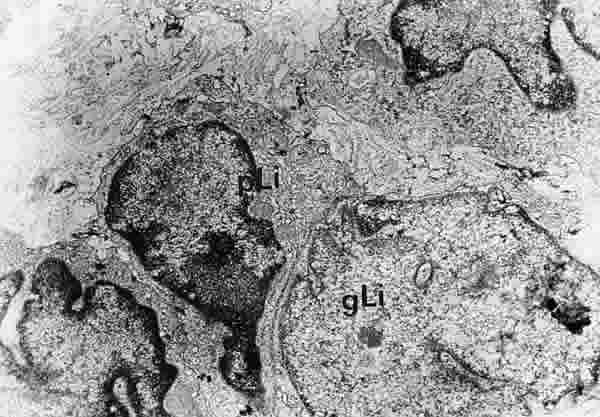

Figura 29

BIOPSIA EN UN PACIENTE CON SS1-GRADO III. EL TEJIDO CONECTIVO PERIGLANDULAR ESTÁ REPLETO DE LINFOCITOS (Li) DE DIFERENTES TAMAÑOS. LOS GRANDES (gLi) TIENEN UN CITOPLASMA ESTRECHO, MIENTRAS QUE LOS LINFOCITOS PEQUEÑOS (pLi) TIENEN ABUNDANTES ORGÁNULOS SUBCELULARES Y CROMATINA DENSA. MICROSCOPIA ELECTRÓNICA. MAGNIFICACIÓN ORIGINAL X8000.